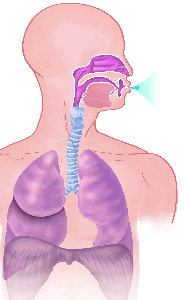

Detailreiche Fotografien aus der medizinischen Praxis ergänzen die Texte; moderne, genaue,

wissenschaftliche Zeichnungen geben Einblick in die Anatomie und die Funktion der Lunge und

anderer Organe.